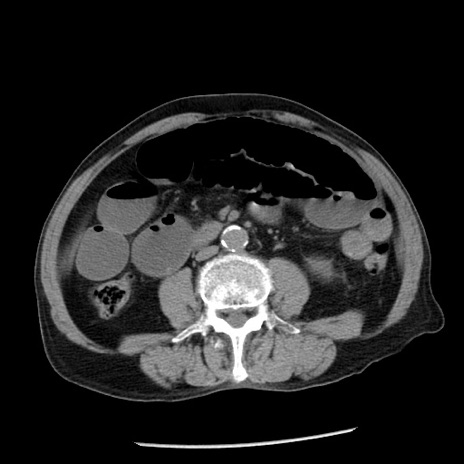

冠状断像